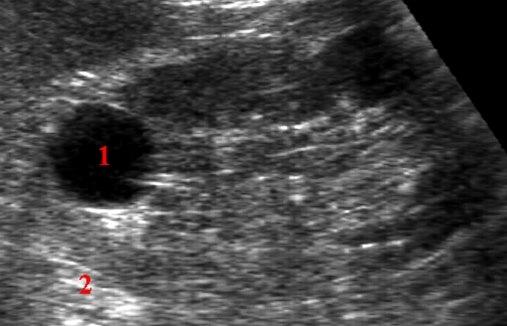

Nyrecyste - ultralydbildeEn nyrecyste er et væskefylt hulrom, en såkalt cyste, som man vanligvis finner i de ytre deler av nyre, i det som kalles nyrebarken. Slike cyster har normalt ingen sammenheng med sykdom og er så godt som alltid godartede.

Nyrecyster oppdages som regel tilfeldig, og de kan for eksempel ses ved ultralyd, CT eller kontrastrøntgen.

Oftest påvises cysten ved ultralyd. Ved denne undersøkelsen kan leger som er godt trente i denne teknikken, i de flest tilfeller med sikkerhet fastslå om cysten er godartet og uskyldig, eller om det er nødvendig med ytterligere undersøkelser.